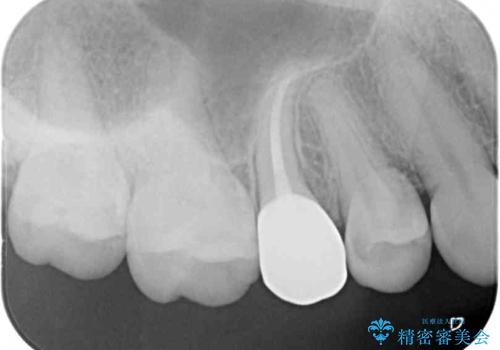

まずは虫歯を除去した上で根管治療を行い、部分矯正により骨内深い位置にまで及んだ健全な部分を引っ張り出すこととしました。

その後骨形成処置を行い、治癒を待って補綴治療を行うこととしました。

かなり深い位置にまで虫歯が及んでいたため、かなりの量を引っ張り出す必要があり、残された歯根は短く小さい状態となりました。

今後も定期的にレントゲンを撮るなど、経過を追っていく必要があります。